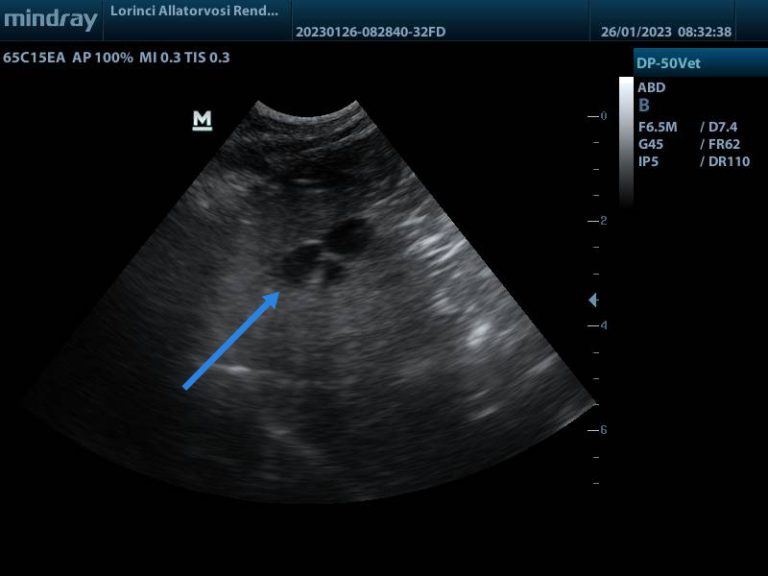

Elváltozás egy macska máján

Ha kedvencünk fizikális tünetei, illetve laborértékei kapcsán májelváltozás felmerül, leggyakrabban hasi ultrahangot javaslunk első körben, amit citológiai és/vagy biopsziás mintavétel, áttétkereső vizsgálatok, CT/MRI, illetve sebészi feltáró műtét követhet, melynek célja lehet a komplett tumor eltávolítása vagy ha ez nem lehetséges, akkor szövettani mintavétel az elváltozásokból, hasi nyirokcsomókból stb.

Hogyan néznek ki a májdaganatok?

A daganatok megjelenése lehet nagy gócos ún. masszív, amikor jellemzően egy nagyobb terimét látunk, vagy több gócos, azaz nodularis, amikor számos kisebb rendellenes terület látható a máj állományában, de lehet diffúz is, amikor a máj egésze érintett.

A hepatocellularis carcinomák általában masszív megjelenésűek. Az epevezető carcinomák esetén mindhárom megjelenési forma előfordul. A mesencyhmalis eredetű szarkómák általában nodularisak. A neuroendokrin carcinoidok jellemzően diffúzak, de a megjelenés alapján sajnos nem lehet diagnózist felállítani.